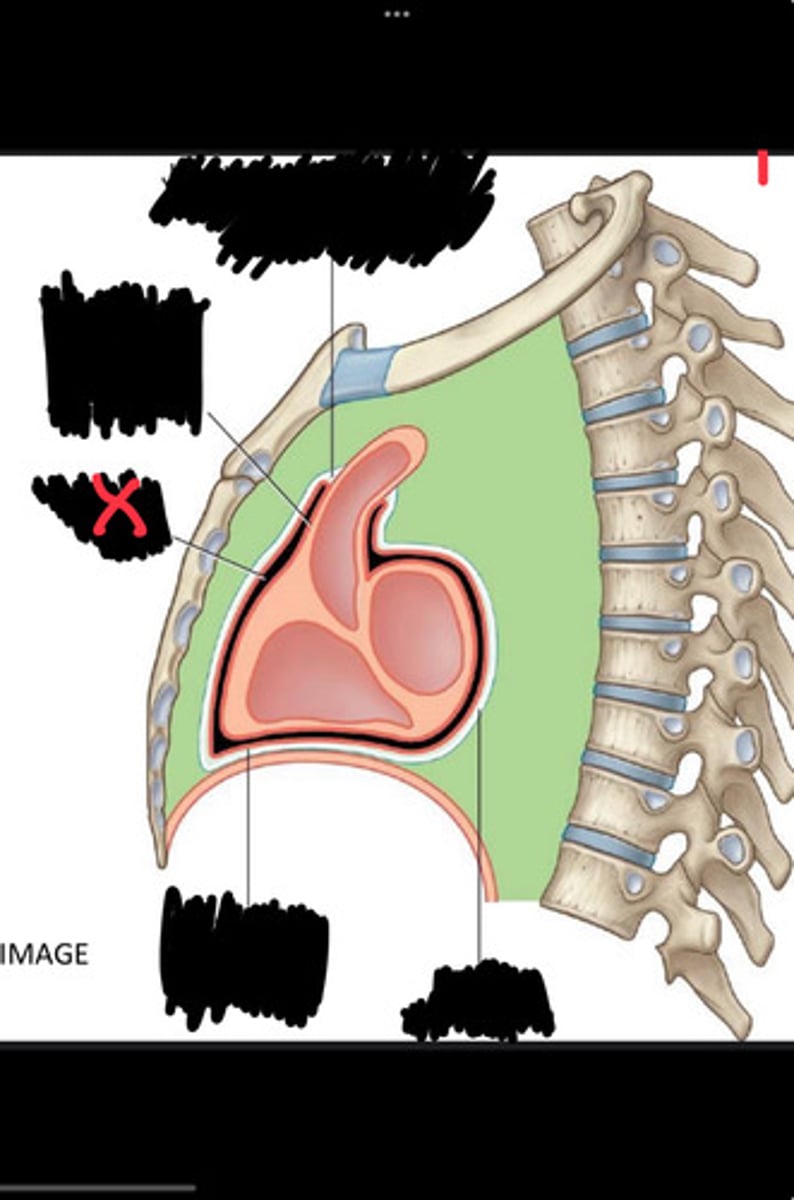

Fibrous pericardium

Parietal layer of serous pericardium

Pericardial cavity

Visceral layer of serous pericardium

Junction between fibrous pericardium and adventitia

Heart

Thoracic aorta

Rib 1